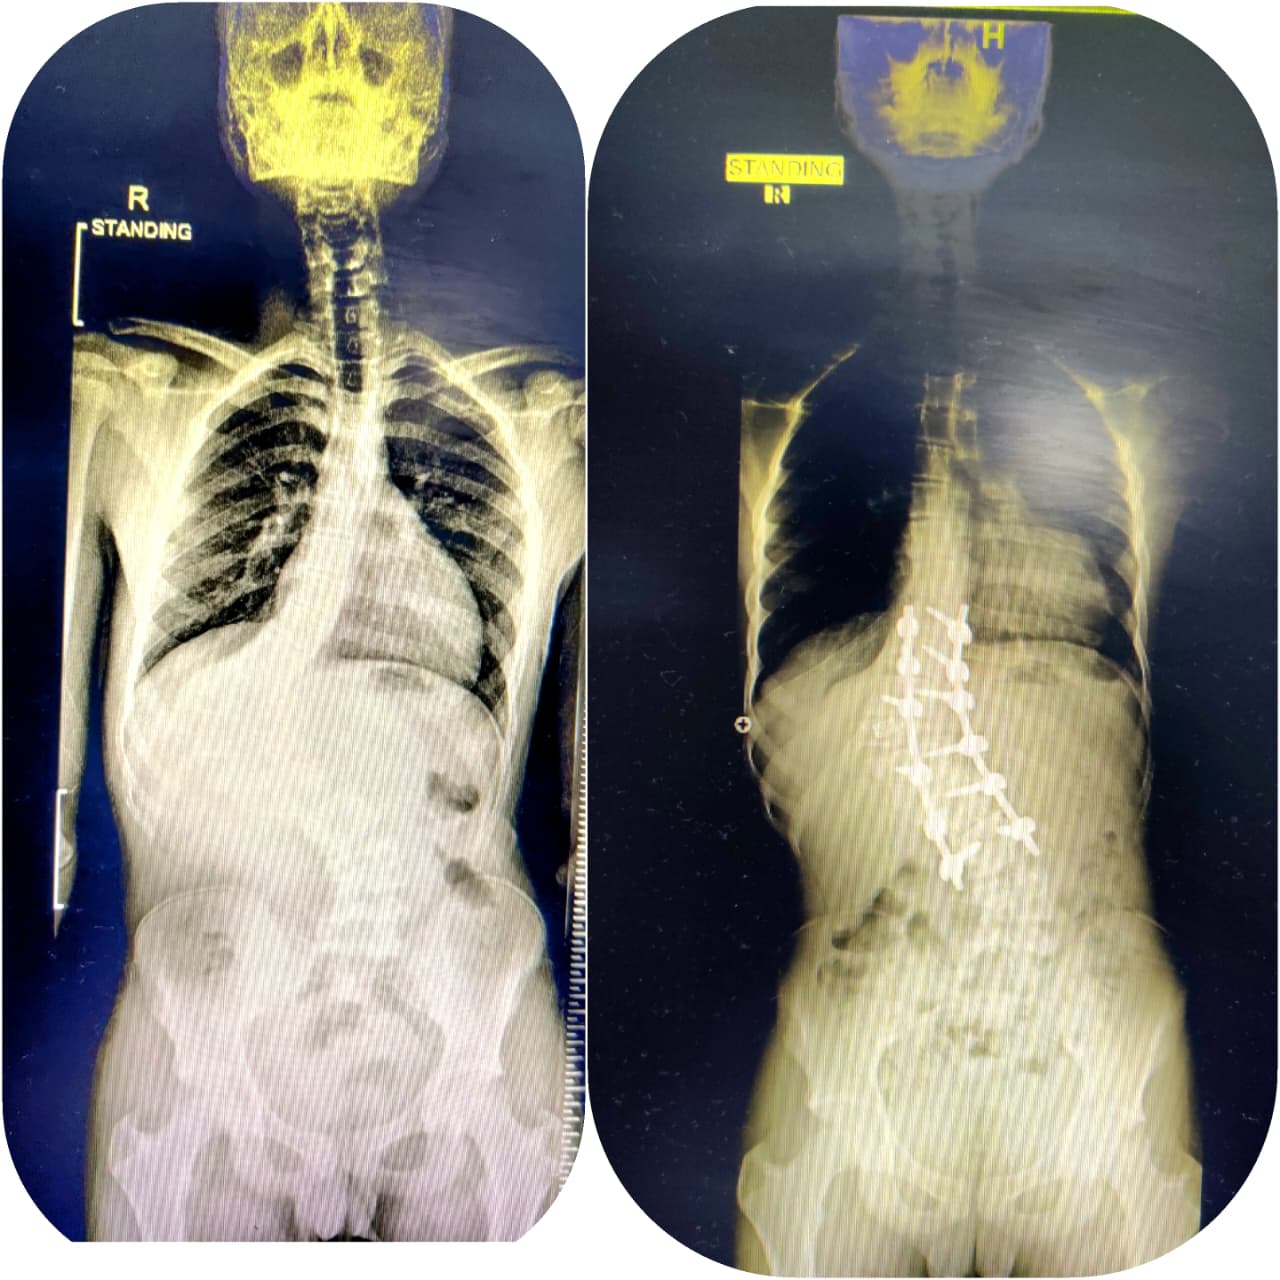

scoliosis